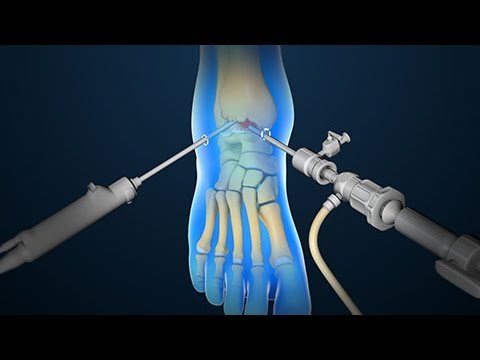

منظار الكاحل هو إجراء جراحي يتم من خلاله إدخال منظار صغير مزود بكاميرا وأدوات دقيقة عبر فتحات صغيرة حول المفصل. تسمح هذه التقنية للطبيب برؤية المفصل من الداخل، ومن ثم معالجة الإصابات دون الحاجة إلى فتح جراحي كبير.

يُوضع المريض في وضعية مناسبة حسب نوع الإجراء، ويتم تنظيف وتعقيم الجلد وتحديد مواضع الفتحات الصغيرة التي سيدخل منها المنظار والأدوات.

2. إدخال المنظار

يقوم الجراح بإدخال المنظار داخل المفصل ويضخ سائلًا معقمًا لتوسيع الحيز وتحسين الرؤية، ما يسمح بفحص الغضاريف والأربطة بدقة عالية.

3. تنفيذ العلاج

يتم تنفيذ العلاج المطلوب مثل إزالة الأجسام الحرة أو تنظيف الغضروف أو إصلاح الأربطة. وتُعد جراحة تنظير الكاحل دقيقة وتتطلب مهارة كبيرة.